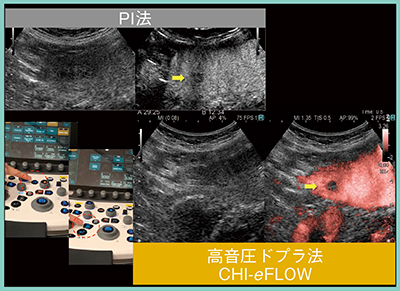

ARIETTAシリーズのContrast Harmonic Imaging(CHI)モードには,Wide-band CHI(WbC),いわゆるPulse Inversion(PI)法がある。セカンドハーモニック(二次高調波:2f0)の技術を応用して,超音波造影剤からの信号を広帯域で受信するため,高感度での画像表示が可能であり,高い空間分解能を有する。

従来,Kupffer相での病変の輝度変化は背景Bモードの影響を受けるため,AM法での評価が望ましいと考えられてきたが,AM法でも判断が難しい症例もある。そこで新たに,背景Bモードの影響を受けることなくKupffer相での輝度変化を評価可能な高音圧ドプラモードCHI-eFLOWがARIETTA 850に搭載された。CHI-eFLOWは,高音圧で造影剤を破壊し疑似ドプラ信号を発生させることで,造影剤を感度良く検出可能となる。操作はわずか2ステップと簡便であり,意図しない造影剤の破壊予防のため,モード遷移後に低音圧のままROIを設定できる。そのため,プローブを体表から離すことなく設定でき,検査を妨げないことも特長である。実際の画像は,輝度変化が非常にわかりやすいものとなっている(図5)。

図5 高音圧ドプラモードCHI-eFLOW